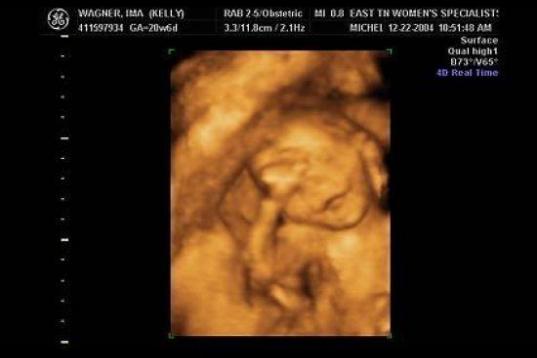

En esta galería puedes ver en fotos como es el desarrollo de un feto de semana en semana:

Desarrollo del feto, en fotos